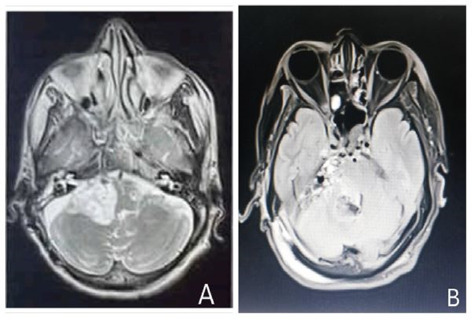

Adenoid cystic carcinoma (ACC) is a rare slow-growing but aggressive malignant tumor arising from the epithelial cells of mucous-secreting glands. Primary intracranial ACC is one of the rarest entity. We report a case of a 61 years old male presenting with difficulty in swallowing, slurring of speech, generalized body weakness. Patient had residual right cerebellopontine angle (CPA) mass causing midline shift and fourth ventricular obstruction on MRI. Patient underwent right retrosigmoid craniotomy with excision of CPA mass. Histopathological examination confirmed the case as primary intracranial ACC.